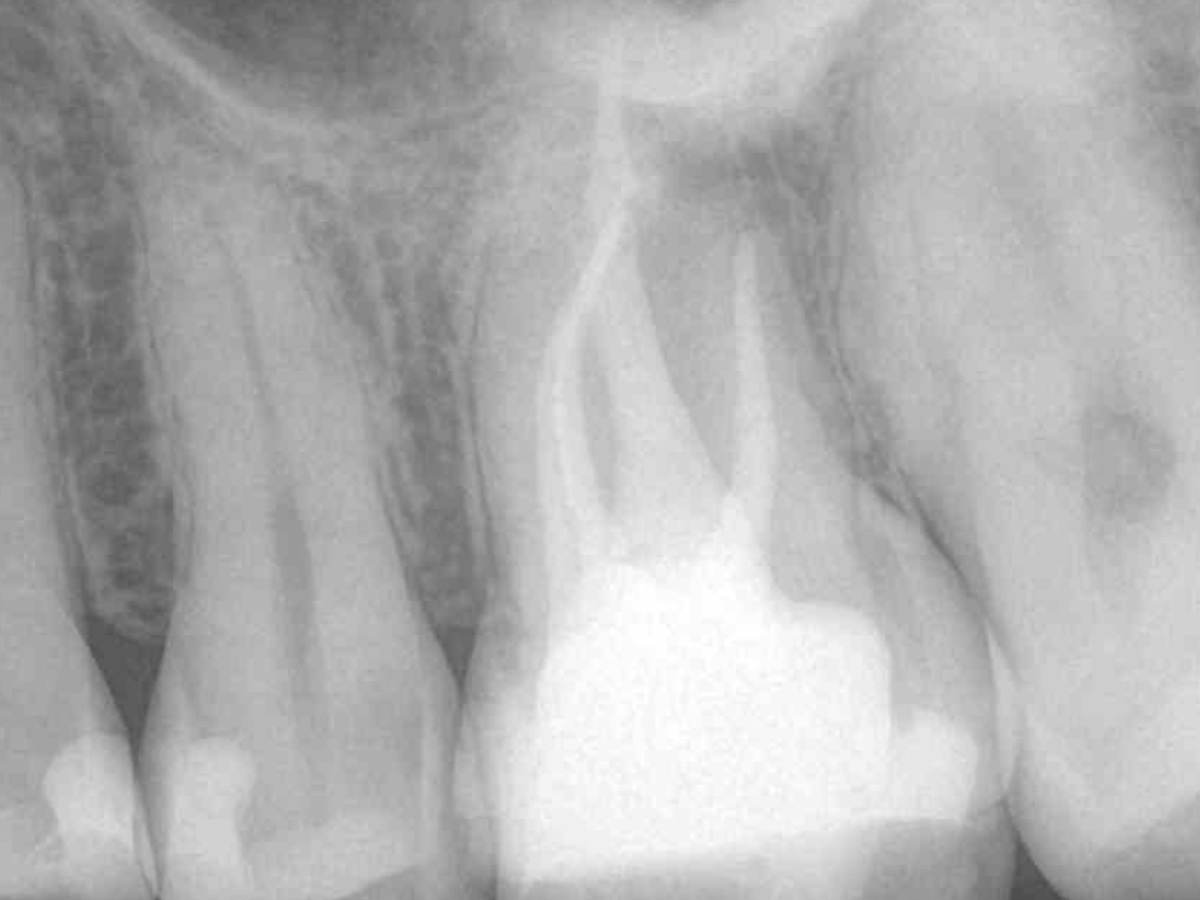

Obturation nach einer erfolgreichen Revision der insuffizienten Wurzelkanalfüllung mit einer symptomatischen apikalen Parodontitis

Der Patient stellte sich mit Aufbissschmerzen vor, wobei die klinische und röntgenologische Untersuchung eine symptomatische apikale Parodontitis an einem bereits wurzelkanalbehandelten Zahn 26 ergab. Die DVT-Aufnahme deutete auf einen unbehandelten zusätzlichen Kanal in der mesio-bukkalen Wurzel hin. Die Darstellung und Behandlung des mb2s sowie die Revision der bereits behandelten Kanäle erfolgte mit dem XP-endo® Rise Shaper bei einer hohen Umdrehungszahl von 2.500rpm.

Abbildung 1

DVT axial

Abbildung 4

Abbildung 5

Wurzelfüllung 26 exzentrisch

Abbildung 7

Wurzelfüllung 26 orthoadial